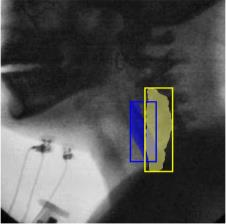

The videofluoroscopic swallowing study (VFSS) is a gold-standard imaging technique for assessing swallowing, but analysis and rating of VFSS recordings is time consuming and requires specialized training and expertise. Researchers have recently demonstrated that it is possible to automatically detect the pharyngeal phase of swallowing and to localize the bolus in VFSS recordings via computer vision, fostering the development of novel techniques for automatic VFSS analysis. However, training of algorithms to perform these tasks requires large amounts of annotated data that are seldom available. We demonstrate that the challenges of pharyngeal phase detection and bolus localization can be solved together using a single approach. We propose a deep-learning framework that jointly tackles pharyngeal phase detection and bolus localization in a weakly-supervised manner, requiring only the initial and final frames of the pharyngeal phase as ground truth annotations for the training. Our approach stems from the observation that bolus presence in the pharynx is the most prominent visual feature upon which to infer whether individual VFSS frames belong to the pharyngeal phase. We conducted extensive experiments with multiple convolutional neural networks (CNNs) on a dataset of 1245 bolus-level clips from 59 healthy subjects. We demonstrated that the pharyngeal phase can be detected with an F1-score higher than 0.9. Moreover, by processing the class activation maps of the CNNs, we were able to localize the bolus with promising results, obtaining correlations with ground truth trajectories higher than 0.9, without any manual annotations of bolus location used for training purposes. Once validated on a larger sample of participants with swallowing disorders, our framework will pave the way for the development of intelligent tools for VFSS analysis to support clinicians in swallowing assessment.